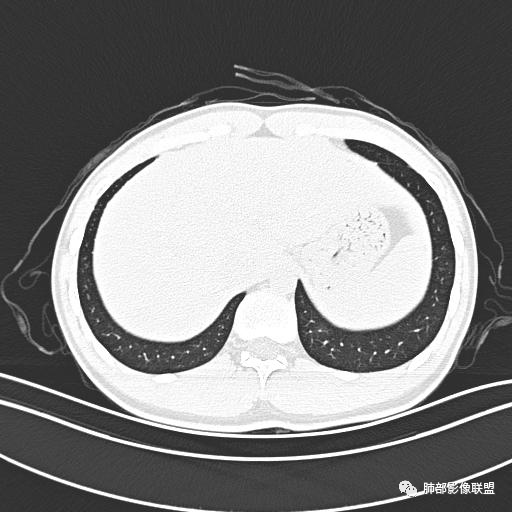

小强:青年,发热,皮疹;双肺散在结节,周围磨玻璃,点晕征,疱疹病毒感染,鉴别荚膜组织胞浆菌,结核。 大雄:青年,急性起病,发热伴全身皮疹2天,抗病毒治疗体温有下降。双肺随机分布大小不等类圆结节,“点晕征”。考虑水痘-疱疹病毒(VZV)血播询问接触史,查体皮疹分布以及形态基本可诊断。 王开金江津中心医院呼吸科:青年男性,起病急,病程短,以发热,皮疹为首发症状,感染指标以单核细胞升高为主,胸部ct双肺多发结界,周围有晕,点晕表现,随机分布,同意於老师意见,水痘疱疹病毒血流感染累及肺。 王秀仙:双肺多发大小不等结节,周围有晕,边缘模糊,呈点晕征表现。青年,急性起病,发热伴全身皮疹2天,抗病毒治疗体温有下降。考虑疱疹病毒。鉴别荚膜组织胞浆菌。 傅昌瑜:19岁男性,发热、全身皮疹2天,单核细胞增高,双肺多发结节,结节边缘见边界不清磨玻璃影。点晕征+发热、全身皮疹+单核细胞增高——考虑水痘-带状疱疹病毒肺炎。 一切∮随缘:年轻男性,发热,皮疹两天,实验室,CRP,PCT增高,影像:双肺多发散在磨玻璃结节,边界欠清,大小不等,呈点晕征改变,以血管束周围分布为主,局部血管束略增粗,其它无明显改变,考虑:1:病毒性肺炎(水痘疱疹病毒?不知道皮肤有无改变)2:真菌(组织胞浆菌,血管侵袭性肺曲霉)3:GPA4:寄生虫(实验室没有看到嗜酸细胞增高) 赵山河:双肺散在结节,周围有晕,边缘模糊,呈点晕征表现。青年,急性起病,发热伴全身皮疹2天,抗病毒治疗体温有下降。考虑水痘—疱疹病毒感染。洪桥爱:青年男性,发热、皮疹2天,伴瘙痒,皮疹于面部首发,之后进展至全身,虽然没有对皮疹进行描述,但是从出疹时间及皮疹进展情况,伴瘙痒,应该就是个水痘患者;CT提示双肺随机分布结节影,部分结节伴有边界不清晕征,考虑水痘血播肺。 刘强:年轻男性,急性起病,皮疹,发热,抗感染治疗体温下降,说明有效。影像表现为散在点晕征,感染类疾病谱(疱疹病毒,真菌,结核),结合年龄,皮肤皮疹,考虑水痘-疱疹病毒性肺炎。 小兜:男性,19岁,发热皮疹两天,颜面部至全身,CRP,降钙素及单核增高。CT示双肺散在小结节,周围伴磨玻璃影,点晕征,考虑为水痘-带状疱疹病毒(varicella-zoster virus,VZV)肺炎 必有路:青年,皮疹+发热+“点晕征”→水痘-疱疹病毒(VZV) 许慧良:青年男性患者,发热、皮疹2天,体温最高38.5℃,第3天皮疹扩展至全身,伴瘙痒,胸部CT:双肺多发随机分布的小结节,结节周边见边界模糊的晕征,考虑水痘病毒感染流心明智:男,19,急性起病,发热伴全身皮疹2天。出疹顺序头→全身,抗病毒有效。胸部CT:两肺多发大小不等类圆形实性小结节影,随机分布,结节周围环绕GGO,边界模糊,呈点晕征。出疹特点是关键,未提示。考虑:血播病毒性肺炎,水痘-疱疹病毒?麻疹?鉴别荚膜组织胞浆菌、TB、血管炎、寄生虫等。 浪迹天涯:病灶多为5-10mm大小结节,结节周围可见磨玻璃样的晕环,常多发,可分布于肺内任何区域,考虑水痘—带状疱疹病肺炎如果短时间内有新的一个区域浸润,更加能说明,